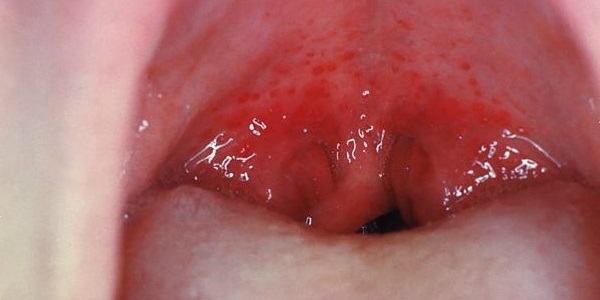

Катаральная: быстро и остро проявляющая себя ангина у детей. Симптомы – першение, слабо выраженная боль в горле, вялость, разбитость, головная боль, ломота в теле.

Температура может колебаться от 37,3 до 39 градусов, либо быть в норме. Катаральная ангина может сопровождаться ознобом, судорогами. Небные миндалины увеличиваются, отекают, наблюдается гиперемия дужек слизистой оболочки глотки;

Герпетическая: характеризуется сильным повышением температурных показателей, обильным слюнотечением, выделениями из носа, появлением пузырьков и язвочек во рту, поражением лимфоидной ткани миндалин и горла, высыпаниями на слизистой носоглотки, увеличением лимфатических узлов в области шеи.

Встречается в большинстве случаев такая ангина у детей до года. Может иметь другие симптомы: боли в животе, рвота, жидкий стул;